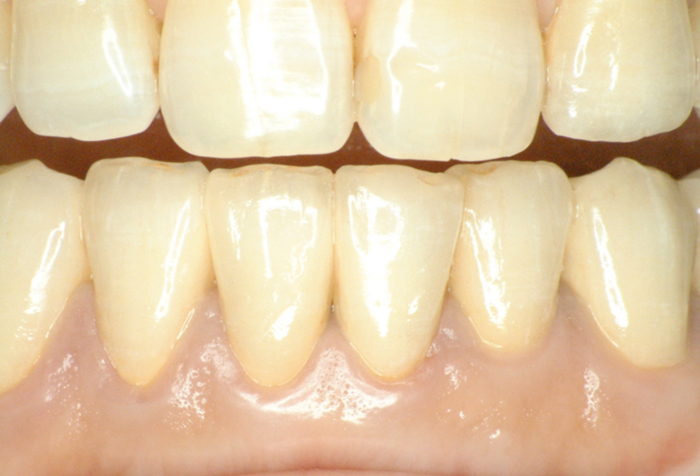

| ●本ケースは、上下顎全歯で患者さんの天然歯が4歯だけ残った症例でした。 結局、上顎にはメタルセラミックスブリッジ補綴を施し、下顎はチャネルショルダーアタッチメントと エクストラコロナル・自家製棒状アタッチメントによるミリング・コンビネーションデンチャーを装備 しています。 ●チャネルショルダーアタッチメントおよび棒状アタッチメントのテクニックに関しては「論文」編 のPDFファイルをご参照くださいませ。 また、製作工程の詳細は「臨床例:補綴用実践的ワックスアップ手順を追う! (コンビ01)」 に良く似た症例を掲載しましたので、ご供覧ください。

| ●下顎右大小臼歯から左犬歯まではメタルセラミックスの連続冠で補綴し、 右大小臼歯、右犬歯および左犬歯、左側切歯の4歯の舌側面にチャネルショルダー内冠 と棒状アタッチメントをミリング加工した。 チャネルショルダー外冠および棒状アタッチメントはパラレルミリング加工しているので、 精密な摩擦抵抗力を持った適合精度が求められます。 内冠の長径および幅径によっても、鋳造システムによる埋没工程の混液比や混水比が 変わってきますので、「コンビネーション用のチェックリスト」を制作し、データを分析しよう。